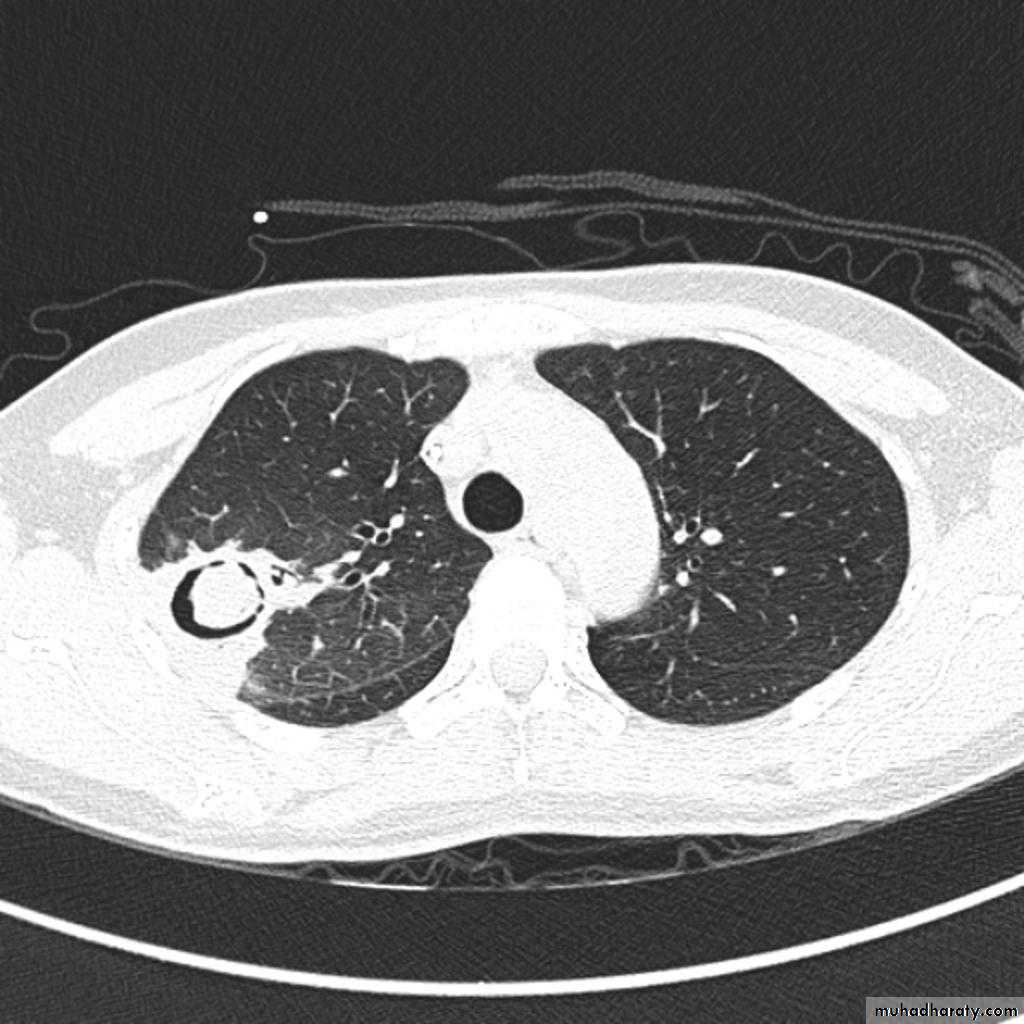

Bronchiectasis

59.Bronchiactasis